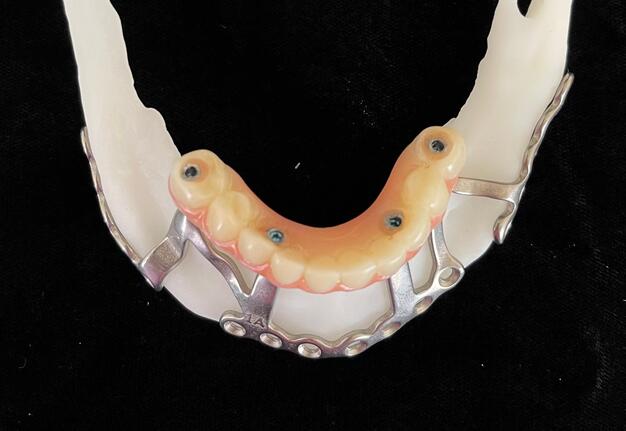

Records for this patient were collected using a dual-scan CBCT and intraoral scanning. A surgical planning session was completed with KLS Martin for the fabrication of a CAD-CAM subperiosteal implant system with immediate loading of a mandibular prototype (Figs 2-5).

A 3D-printed mandibular model with the subperiosteal system and prototype in place was also fabricated (Figs 6 and 7).

2. Back-Pour Cast Fabrication

Analogs were attached to the prototype, and a back-pour cast was fabricated using Type IV Silky-Rock dental stone (Whip Mix). Reference notches were added to aid in digitization (Fig 12).

3. Digital Data Capture

• Stereophotography scans of the cast were performed with the prototype in place and after removal with ICam4D scan bodies using Trios 4 Wireless Pod (3Shape) (Figs 12-14).

5. Final Prosthesis

The refined prototype was rescanned on the back-pour cast, and a definitive monolithic implant supported fixed zirconia prosthesis was fabricated and successfully delivered (Figs 16 and 17).